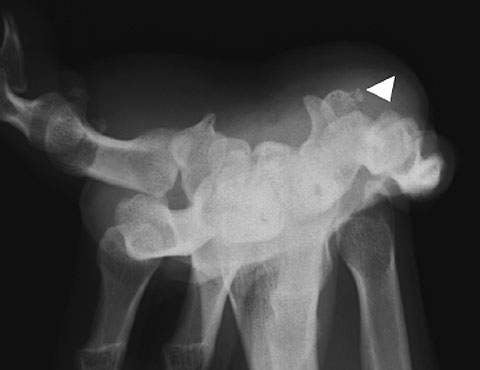

Case 1 – 29-year-old male: the patient visited the hospital complaining of unexplained pain in the right volar wrist during flexing for the past few months. Carpal tunnel radiography confirmed calcification at the ulnar side of the pisiform bone (Fig. 9), although it was not apparent in general radiographs from two directions. Lateral tomosynthesis of the wrist joint revealed a calcified deposit. Another tomosynthesis image taken two months later confirmed repair at the exfoliated area (Fig. 10).